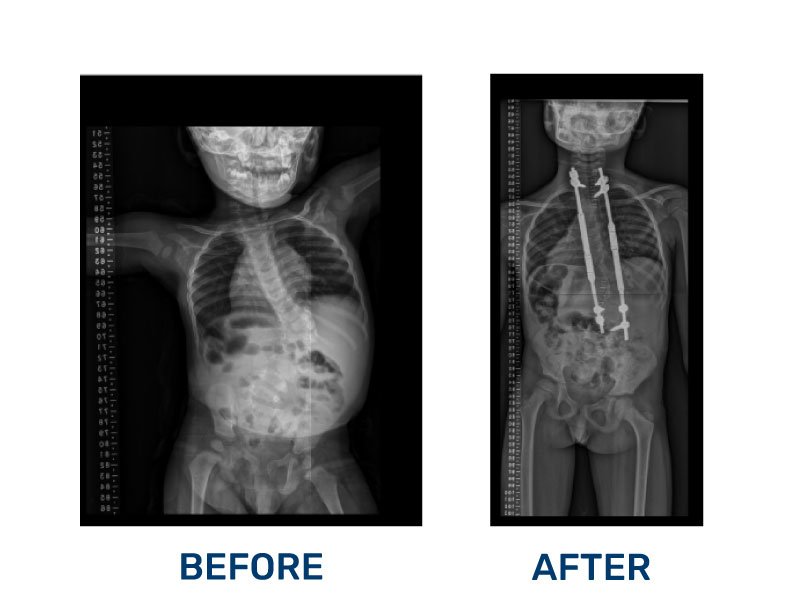

Scoliosis

Determined to find the best care, Ryan’s mother sought medical help, leading them to the Foundation of Orthopedics and Complex Spine (FOCOS) in 2019. After a thorough evaluation, Ryan underwent his first life-changing surgery. However, in 2024, he required a second procedure to fully correct his condition.

In December 2024, Ryan was admitted to FOCOS once again, and thanks to the expertise of his surgical team, his operation was a complete success—free of complications.